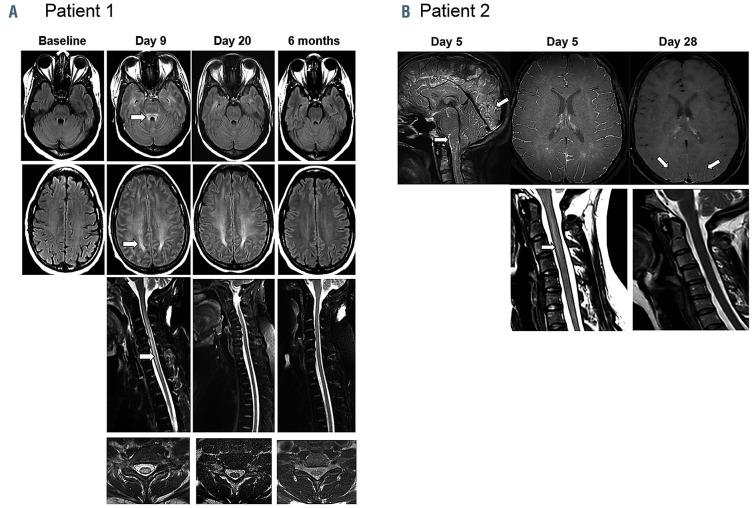

Acute leucoencephalomyelopathy and quadriparesis after CAR T-cell therapy.